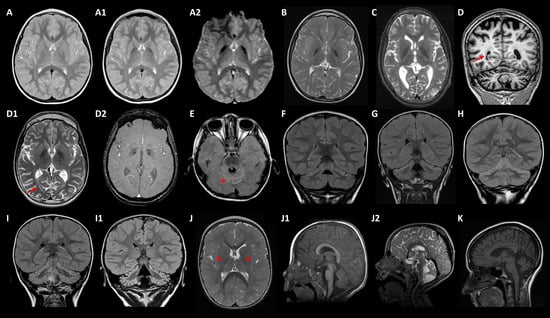

| Patient Sex | Gene | Origin | Presentation Inheritance | Disease (OMIM) | Age of Onset Age at Testing | Early Symptoms | Brain MRI | Additional Clinical Features |

|---|---|---|---|---|---|---|---|---|

| MD-208 Female | CASK | Spain | de novo XLD | Mental retardation and microcephaly with pontine and cerebellar hypoplasia (300749) | 1 mo 3 yo | Hypotonia Microcephaly DD | Severe PCH | Mild limb dystonia, choreoathetosis, progressive scoliosis from 3 yo |

| MD-216 Male | CPLANE1 | Morocco | Familial AR | Joubert syndrome 17 (614615) | 1 yo 10 yo | DD Hypotonia, ataxia OMA | Molar tooth sign Cerebellar hypoplasia | ID, ataxia and OMA improve with age |

| MD-122 Female | EXOSC3 | Spain | Sporadic AR | Pontocerebellar hypoplasia type 1B (614678) | 3 mo 3 yo | Hypotonia, axial hyperextension, strabismus | Progressive vermis atrophy | Spasticity progressing to flaccid paralysis from 3-yo, g-tube feeding, neurogenic EMG pattern, exitus at 4 yo |

| MD-012 Male | EXOSC3 | Spain | Sporadic AR | 4 mo 8 yo | Hypotonia, DD | Progressive vermis atrophy | Spasticity from 4 yo, axonal neuropathy with loss of tendon reflexes from 5 yo, g-tube feeding, limb dystonia from 6 yo | |

| MD-018 # Female | FBXO7 | Morocco | Sporadic AR | Parkinson disease 15 (260300) | 2 yo 21 yo | Mild DD, infection-triggered acute ataxia at 2 yo | CA from 10 yo Brain iron deposits from 15 yo | Absence epilepsy from 5 yo, acute encephalopathy at 12 yo, progressive deterioration, spastic paraparesis, drug-resistant seizures, optic neuropathy, parkinsonism from 15 yo |

| MD-137 Male | FUCA1 | Greece | Sporadic AR | Fucosidosis (230000) | 3 yo 10 yo | Speech difficulties, gait disturbances | GP T2 hypointensity from 10 yo | Static encephalopathy, progression of gait disorder with dystonia, ID, dysmorphic features, ADHD symptoms, motor stereotypes |

| MD-020 Female | GLB1 | Spain | Sporadic AR | GM1-gangliosidosis (230500, 230600, 230650) | 3 yo 12 yo | Speech difficulties, motor deterioration | Brain iron deposits from 10 yo | Oromandibular dystonia, dysarthria, neuropathy, spasticity, scoliosis |

| MD-270 Female | HEXA | Spain | NA AR | GM2-gangliosidosis (272800) | 26 yo 23 yo | DD, hypotonia | CA | Cerebellar syndrome, stereotyped behaviour, progressive cognitive decline |

| MD-320 Male | ITPR1 | Senegal | de novo AD | SCA15 (606658) SCA29 congenital nonprogressive (117360) | 3 mo 5 yo | DD, hypotonia, gaze-evoked nystagmus | CA Cerebellar cortical hyperintensity from 3 yo (upper > lower hemispheres) | Ataxia, NPCA, strabismus, ID, mild lower limbs spasticity |

| MD-106 Male | ITPR1 | Morocco | de novo AD | <1 yo 6 yo | DD, hypotonia | CA Cerebellar cortical hyperintensity from 3 yo (upper > lower hemispheres) | Ataxia, NPCA, strabismus, gaze-evoked nystagmus, ID, lower limbs spasticity | |

| MD-041 Male | ITPR1 | Spain | de novo AD | 2 mo 3 yo | Gaze-evoked nystagmus, hypotonia | CA Cerebellar cortical FLAIR hyperintensity at age of 4 (upper > lower hemispheres) | Ataxia, NPCA, strabismus, abnormal ocular movements, ID | |

| MD-200 Male | KIF1A | Spain | de novo AD | NESCAV syndrome (614255) | <1 yo 12 yo | DD, microcephaly, nystagmus | CA | Ataxia, NPCA, lower limbs spasticity, seizures (4 yo), dysphagia, intellectual disability, axonal neuropathy, optic atrophy (9 yo) |

| MD-189 Male | KIF1A | Portugal | de novo AD | SPG30 (610357) | 12 mo 22 yo | DD, visual deficit | CA Brain iron deposits from 17 yo | Ataxia, NPCA, optic atrophy, stuttering (2 yo), lower limbs spasticity (3 yo), cognitive regression (4 yo), peripheral neuropathy, seizures (14 yo) |

| MD-299 Male | KIF1A | Spain | de novo AD | SPG30 (610357) | 11 mo 9 yo | DD, hypotonia | CA Cerebellar cortical and deep WM FLAIR hyperintensity | Ataxia (2 yo), NPCA, acquired microcephaly, lower limbs spasticity (3 yo), cognitive impairment, no regression |

| MD-319 Male | LRRK2 | Morocco | Sporadic AR | Parkinson disease (607060) | 5 yo 14 yo | Tremor | Normal | Hands tremor, cervical tremor, mild bradykinesia, hoarseness voice (13 yo) |

| MD-277 # Male | NR4A2 | Spain | de novo AD | AD early-onset dystonia-parkinsonism with intellectual disability (601828) | 12 yo 29 yo | Mild DD from 1 yo | Normal | Borderline IQ (77; 7 yo), motor tics from 16-yo, dystonia and parkinsonism from 28 yo |

| MD-173 Female | PDGFB | Spain | Familial AD | Basal ganglia calcification idiopathic 5 (615483) | 19 yo 19 yo | Postural and intentional tremor | Calcifications | Tremor |

| MD-252 Male | PNKD | Spain | Familial? AD | Paroxysmal nonkinesigenic dyskinesia 1 (118800) | 49 yo 49 yo | Paroxysmal dystonia | Normal | Dystonia, parkinsonism |

| MD-341 Female | PLA2G6 | Morocco | Sporadic AR | Infantile neuroaxonal dystrophy 1 (256600) NBIA2B (610217) Parkinson disease 14 (612953) | 12 mo 5 yo | Ataxic gait, DD | CA Cerebellar cortical FLAIR hyperintensity | Ataxia, dysmetria, hypotonia, spasticity, axonal motor impairment, optic atrophy, intellectual disability |

| MD-181 Male | PLEKHG2 | Spain | Sporadic AR | Leukodystrophy and acquired microcephaly with or without dystonia (616763) | 1 mo 6 yo | Hypotonia, DD | Thalamic lesions CA | Spastic-dystonic tetraparesia from 6 mo, bilateral cataracts, OMA, neuropathy |

| MD-323 Male | PMPCA | Spain | Sporadic AR | SCAR2 (213200) | 21 mo 9 yo | Motor development delay, ataxia, nystagmus | CA Cerebellar cortical hyperintensity | Ataxia, NPCA, mild cognitive impairment |

| MD-174 # Male | PRDX3 | Morocco | Sporadic AR | NA | 2 yo 3 yo | Non-triggered acute cerebellar syndrome | Rapid progression of CA | Ataxia, chronic cerebellar syndrome following acute onset, demyelinating neuropathy from 5 yo |

| MD-296 Male | QARS1 | Morocco | Sporadic AR | Microcephaly, progressive seizures, and cerebral and cerebellar atrophy (615760) | 18 mo 13 yo | Febrile seizures, DD, atypical absences | CA | ID, language impairment, drug-resistant epilepsy with non-motor and motor seizures |

| MD-126 # Female | REEP1 | Spain | de novo AD | SPG31 (610250) | 33 yo 35 yo | Parkinsonism | Calcifications | Parkinsonism, tremor, spasticity, dystonia, slow saccades, dysarthria |

| MD-307 Male | RPGRIP1L | Spain | Sporadic AR | COACH syndrome (216360) Joubert syndrome 7 (611560) Meckel syndrome 5 (611561) | 1 mo 1 yo | Hypotonia, nystagmus, strabismus | PCH | Profound DD, g-tube feeding, awake apneas, seizures, dyskinesia, exitus at 24 mo |

| MD-159 # Male | SPG7 | Spain | Sporadic AR | SPG7 (607259) | 17 yo 26 yo | Dystonia, postural instability, dysarthria | CA | Mild dystonic gait with mild spastic-ataxia gait, dysmetric saccades, gaze-evoked nystagmus, intention tremor |

| MD-219 # Male | SPTBN2 | Spain | de novo AD | SCA5 (600224) | 4 mo 11 yo | Hypotonia, transient upgaze deviation | Severe CA Cerebellar cortical hyperintensity | Ataxia, NPCA, moderate ID |

| MD-207 # Male | SPTBN2 | Spain | de novo AD | SCA5 (600224) | 12 mo 8 yo | Motor delay, DD | Severe CA Cerebellar cortical hyperintensity | Ataxia, NPCA, ADHD, borderline IQ |

| MD-153 Male | TPP1 | Cuba | Sporadic AR | Ceroid lipofuscinosis neuronal 2 (204500) SCA7 (609270) | 5 yo 13 yo | Speech delay, stuttering, motor clumsiness | GP FLAIR low signal, cerebral and CA, white matter T2-high signal | Limb and orofacial dystonia from 11 yo, spasticity, cognitive decline, no seizures |